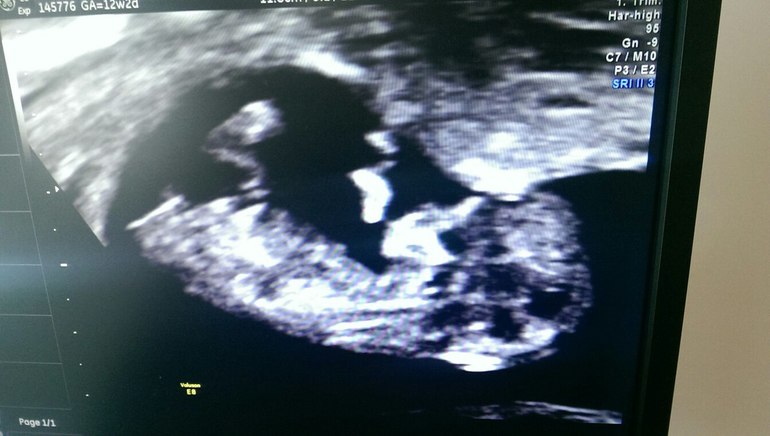

2. УЗИ - на кабинете четко написано, чтоб сопровождающих не было, так администратор, даже папаш не пускала близко к этим кабинетам))) . Зашла в кабинет, растелила пеленку и легла (узи делали по животику). Поворачиваю голову к монитору и вижу моего лягушонка , потому что подругому я назвать не могу ... и все... меня накрыло, но я держалась... по щекам скатывались слезки счастья...

НАШИ РАЗМЕРЫ:

КТР 58,9мм

ТВП 1,30 мм

размер головы (БПР) 18,7 мм

Окружность головы 69,0 мм

Окружность животика 57,0 мм

Длина бедер 6,7 мм

"Внутричерепное" пространство определяется 2,00 мм

Но у меня нет размеров носика, а просто написано, что - Кость носа определяется , хм....

Оценка анатомии плода, все в норме, все определяется)))

Сердечко бьется 156 уд/мин , ритмичное

Моя молявочка, спокойная была, все было фиолетово, что на нее смотрят, то ли спал, то ли спокойный в папу))))

развиваемся мы срок в срок 12+2, что по ПДМ, что по КТР, срок родов нам поставили на 03.10.2016

фото мне не дали((( разрешили только с монитора узи сфотографировать((((, но я вышла довольная, узистка потологий не увидила, значит и по крови у нас все должно быть на 100% круто!